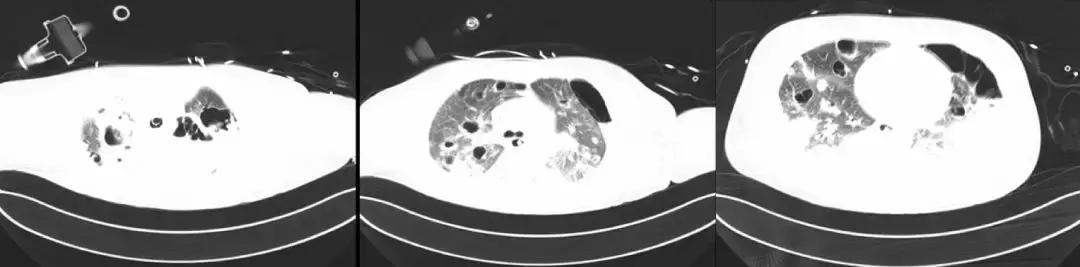

*疾病转归

7月27日胸部CT

7月27日成功拔除气切插管;口服利奈唑胺序贯治疗;

8月1日好转出院,转回中心医院继续康复治疗。